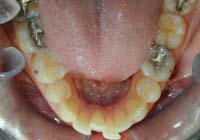

Treatment Time: 9 months

Aligners: 19 Lower